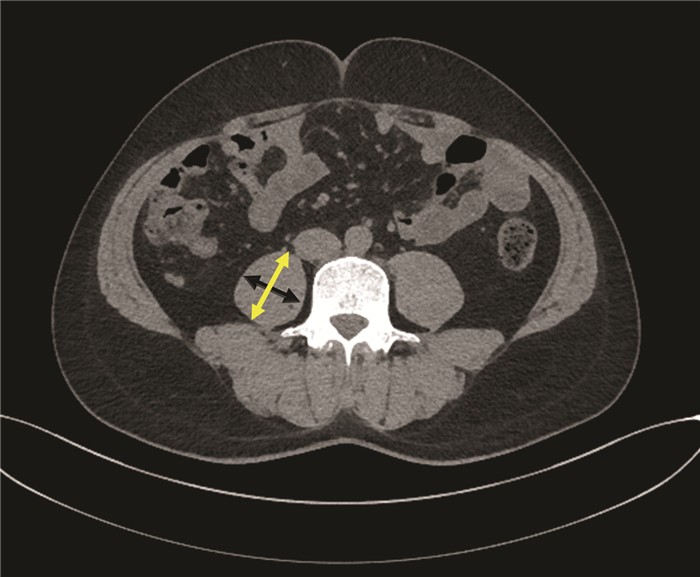

A case of portal biliopathy

Peng JIANG, Shupeng WANG, Yahui LIU

2022, 38(2): 430-432. DOI: 10.3969/j.issn.1001-5256.2022.02.034

Abstract(661) HTML (236) PDF (2686KB)(38)

Abstract: